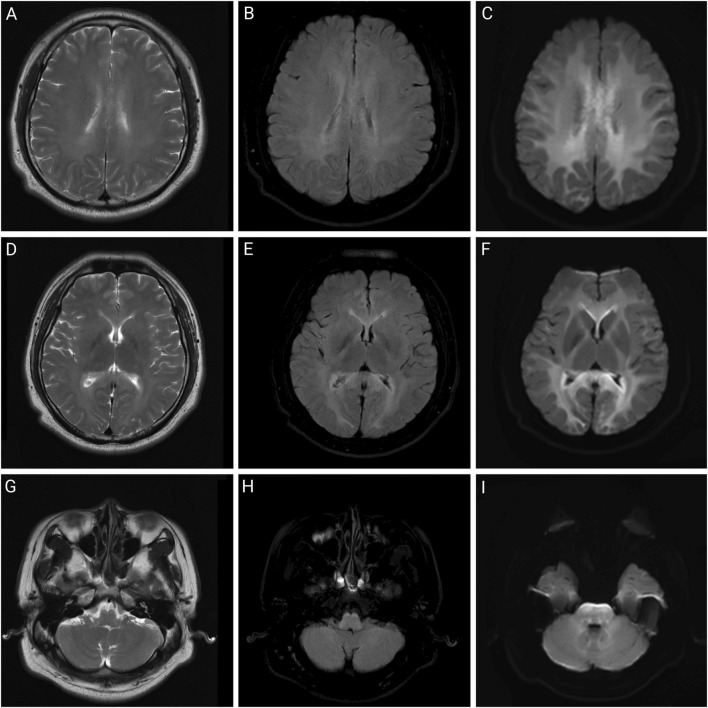

Results: All four patients worked in the same factory before admission; three worked in the same workshop, while one worked in the product inspection department. Patients three and four had no obvious clinical manifestations, whereas patients one and two primarily presented with hyperhidrosis, fever, and neurological symptoms. Laboratory tests revealed abnormalities in blood counts, liver and kidney function indicators, and cardiac enzyme profiles in some patients. Magnetic resonance imaging revealed varying degrees of abnormal signal changes in the brain and spinal cord in Patients 1, 2, and 3. After comprehensive treatment with blood purification, organ protection, and symptomatic treatment, chlorfenapyr blood concentrations in patients 1, 2, and 3 decreased. Patients one and three were discharged on the 30th and 14th days of admission, respectively, while patient 2, whose condition worsened, died on the 11th day of treatment after unsuccessful resuscitation.

Abstract Image